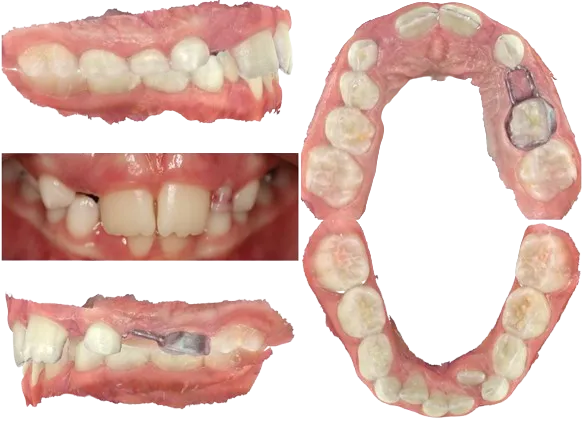

9 Year Old Female with Deep Bite & Severe Crowding

SUBJECTIVE: She presented with her parents and concerns of crowding along with esthetics.

OBJECTIVE: She had premature loss of #i with a band and loop appliance to maintain space which was beginning to submerge on the loop end. Her molars were a flush terminal plane on the right and left, with minimal overjet. Her overbite was 90% and impinging on the palatal tissues. There was insufficient space for the upper laterals to erupt and the lower laterals had erupted lingually with #23 severely ectopic. Overall the arches appeared slightly constricted but with no crossbite, no report of sleep disordered breathing, competent lips, and true consistent nasal breathing during the consult, palatal expansion was not indicated.

ASSESSMENT: Treatment goals were to improve the overjet, decrease the overbite, create space for upper laterals, align teeth, and broaden the arch forms. Option 1: Upper and lower 2x6 (brackets on anteriors as well as first molars). Option 2: Upper and lower Invisalign. Estimated tx time: 9-12mo.

PLAN: Patient and parents elected to proceed with Invisalign.